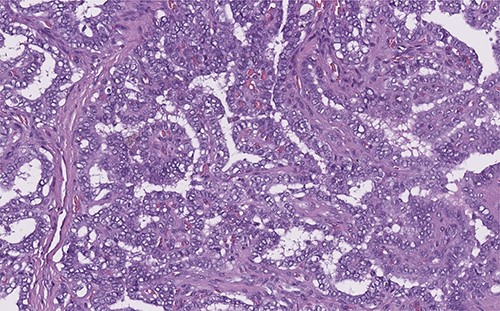

Two months ago, the patient began with a volume increasing mass in the anterior side of the neck, without any added symptoms. The patient visited a physician who asked for a thyroid ultrasound, which was performed on august 16th of the present year. The study showed a midline-neck heterogeneous cystic mass. The follow-up plan included a contrast-enhanced computer tomography scan, to analyze the possibility of a neo proliferative mass, as the radiology specialist suggested. The scan was performed 2 days later, and it revealed a solid cystic tumor, with multiple septa, localized on the midline adjacent to the thyroid gland and its pyramidal lobe (Fig. 5). The histopathology report suggested a thyroglossal duct cyst related to a papillary-type thyroid cancer (Fig. 6).

Solid cystic tumor, with multiple septa, localized on the midline adjacent to the thyroid gland.

Papillary thyroid carcinoma: true papillae with multiple branching, stromal stalk with microvessels (left). Note the optically clear (empty, ground-glass) nuclei with thick nuclear membrane (H&E, high power).